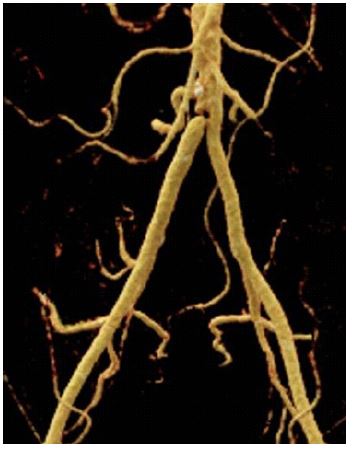

A female patient, 71 years old, active smoker, with arterial hypertension and diabetes, was admitted with right inferior limb rest pain. The patient was submitted to Angioct-Scan which demonstrated common iliac arteries bilateral occlusion. The patient was submitted to endovascular surgery with an iliac kissing stent and implant of Wrapsody 8×50 mm at the right common iliac artery and Wrapsody 7×75 mm at the left common iliac artery, followed by post-dilatation with a catheter balloon. (Figure 3). The patient was discharged from the hospital first day post-operative and 1-month follow-up showed endoprosthesis patency with complete resolution of the previous symptoms.

Figure 3: Iliac kissing stent and implant of Wrapsody 8×50 mm at the right common iliac artery and Wrapsody 7×75 mm.